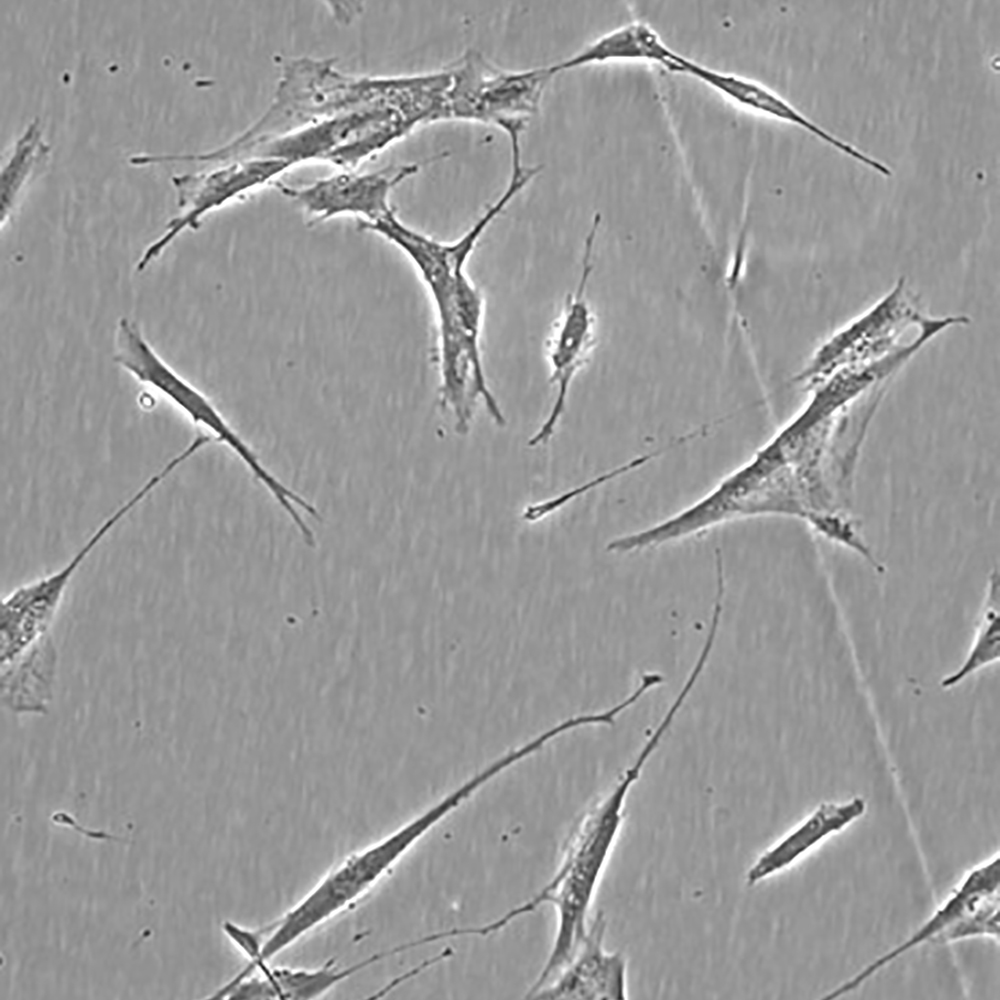

產品名稱 Hs 606.T

中文名稱 人乳腺癌細胞

組織來源 乳腺癌;女性

生長特性 貼壁

培養基 H-DMEM,90%;FBS,10%;雙抗。